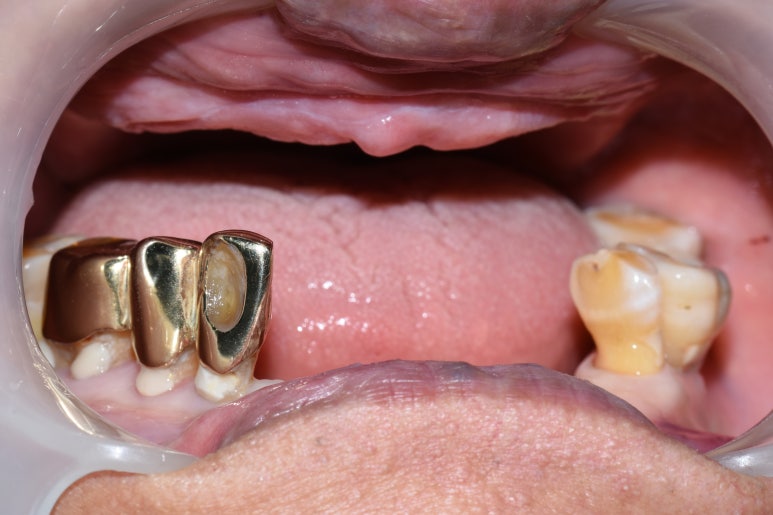

7.아래쪽 임플란트 최소 2개 심고 틀니 연결하여

덜 움직이는 틀니

8.다른 치과에서 한 아래틀니가 너무 아픈 환자분

아래 2개 임플란트를 심고 임플란트 틀니로 변경

아래치아 하나도 없음. 임플란트 심기 전

↓

아래 임플란트틀니를 위한 임플란트 2개 식립

기존 다른치과 전체틀니에 임플란트를 연결하여 움직이지 않게 해드렸습니다.